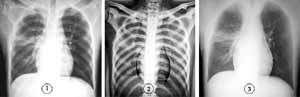

2.2.1 胸部外伤 DR标准影像和能量减影影像对135例胸部外伤患者肋骨骨折的诊断结果见表1。以能量减影胸片作出的诊断为标准,胸片表现正常者97例,肋骨骨折38例,其中单根肋骨骨折23例,多根肋骨骨折15例;单纯肋骨骨折30例,肋骨骨折合并肺部损伤实变5例,见图1~3,肋骨骨折合并气胸3例。骨骼影像和软组织影像分别能更清晰地显示肋骨骨折和肺部损伤,提高病变的检出率。骨骼影像显示骨性胸廓方面优于标准影像,特别是纵隔、心影和膈下结构重叠的肋骨。在标准影像的基础上,4例患者发现了更多肋骨骨折,1例患者发现了肺部损伤实变。

图1 标准影像 图2 骨骼影像 图3 软组织影像